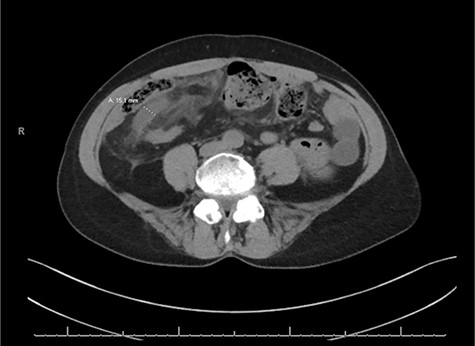

A CT of the abdomen and pelvis without contrast was obtained on admission and revealed a dilated appendix up to 1.5 cm in size with no evidence of obvious appendicolith (Fig. 1). There was evidence of extensive mesenteric edema in the right lower quadrant of the abdomen. It was felt that these findings were consistent with appendicitis with possible early rupture pattern. Due to her history and likely early ruptured appendicitis, she was felt to be a high surgical risk and she was initially treated on the interval appendicitis pathway. This included IV antibiotic therapy and a repeat CT scan of the abdomen/pelvis 48 h after initial presentation. She was also placed on a heparin drip and her Coumadin and Plaquenil was held.

Axial slice of the CT of the abdomen/pelvis demonstrating a dilated appendix up to 1.5 cm in size with mesenteric edema in the right lower quadrant of the abdomen.